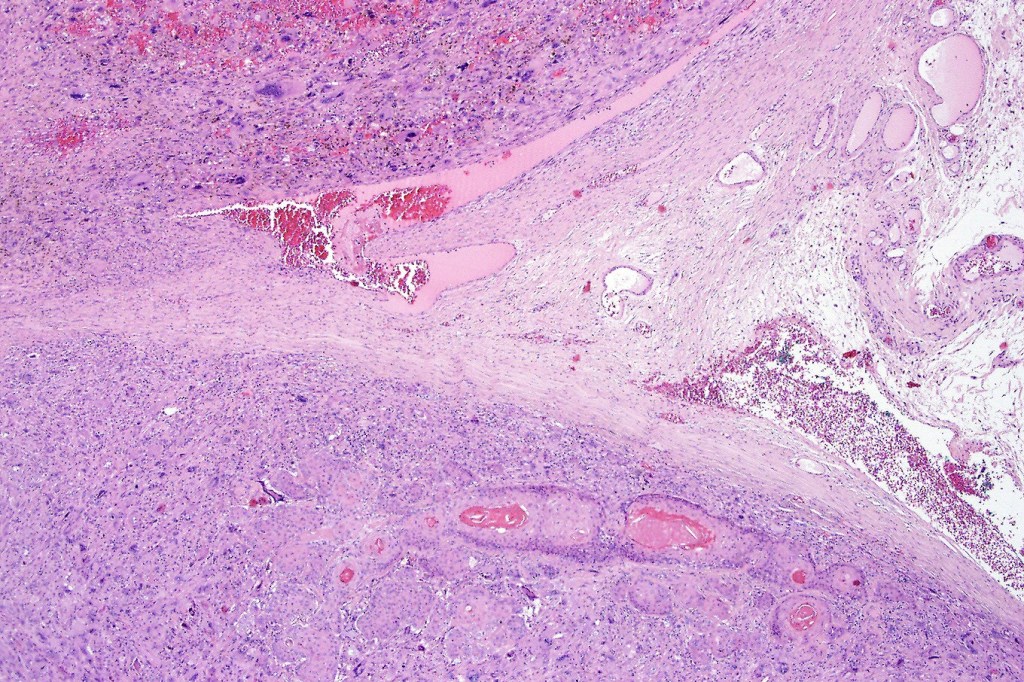

•Biphasic tumor

•Admixture of squamous carcinoma & pleomorphic spindled cell, osteoid, chondroid, MFH-like +/- osteoclast-like giant cells & rarely, smooth muscle, skeletal muscle, myofibroblastic or angiosarcomatous elements